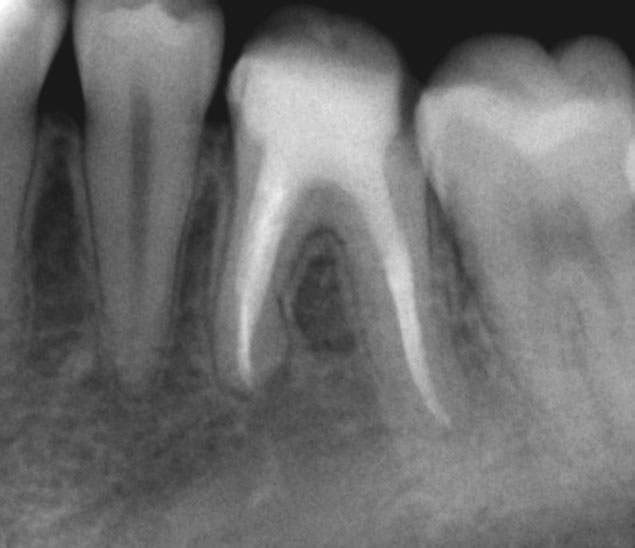

Pre-op

Pain in mandibular first molar after endo. Previous dentist unable to locate mesial canals. Obturated only the distal canal. Patient has generalized periodontal problems as well.

Pre-op, EDTA for 1 minute, After 1 minute EDTA

Red arrows show the two “white spots” indicating the calcified mesial canals.

Missed second distal canal (red arrow)

Pre-op & Post-op